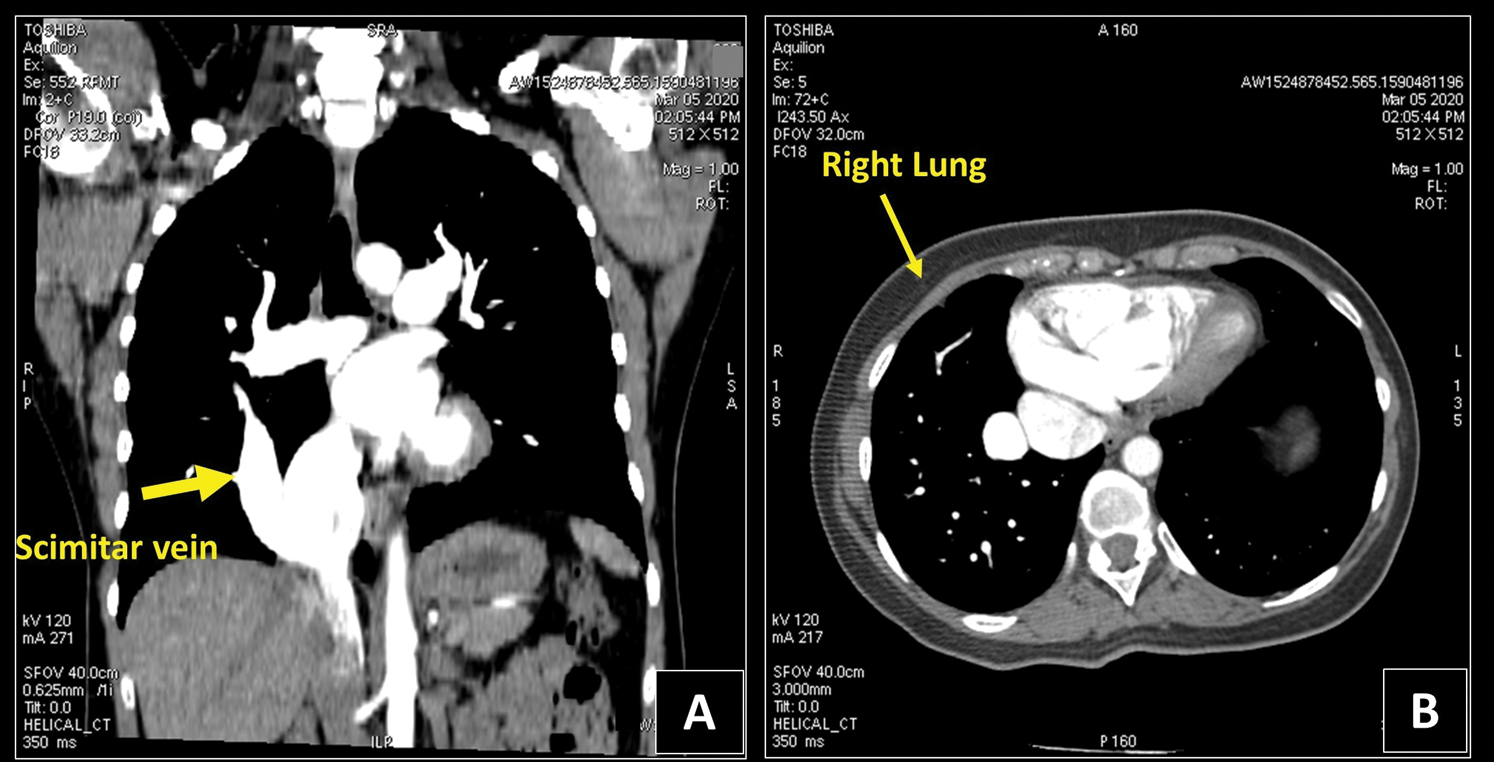

A Computed Tomography Angiography (CTA) showed no filling defects in both pulmonary arteries but a partial anomalous pulmonary venous return (PAPVR), with a large vein originating from the right lung parenchyma draining into the IVC, complete absence of the usual right inferior pulmonary vein and a hypoplastic upper right vein draining into the LA. The right lung was slightly hypoplastic compared to the left, with right basal congestion, suggesting Scimitar Syndrome (Fig. 5).

Figure 5: Chest CT. Panel A. The coronal CT view reveals an anomalous enlarged right vein, draining blood from the right lung to the inferior vena cava (yellow arrow). Panel B. The right lung is hypoplastic and more congested if compared to the left one at the CT exam. CT = Computed Tomography

A coronary CTA was then performed to rule out CAD, excluding both stenosis and abnormal origin of coronary arteries. Furthermore, the atrial septum was confirmed intact.